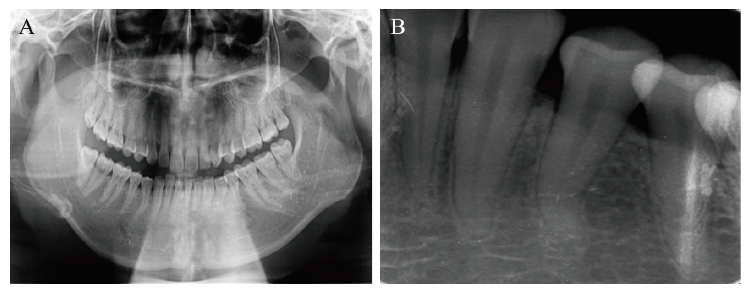

二、专科检查及治疗计划拟定

图2 一例牙龈瘤患者术前的影像学检查结果

注:A为术前全景X线片检查结果;B为术前根尖X线片检查结果。